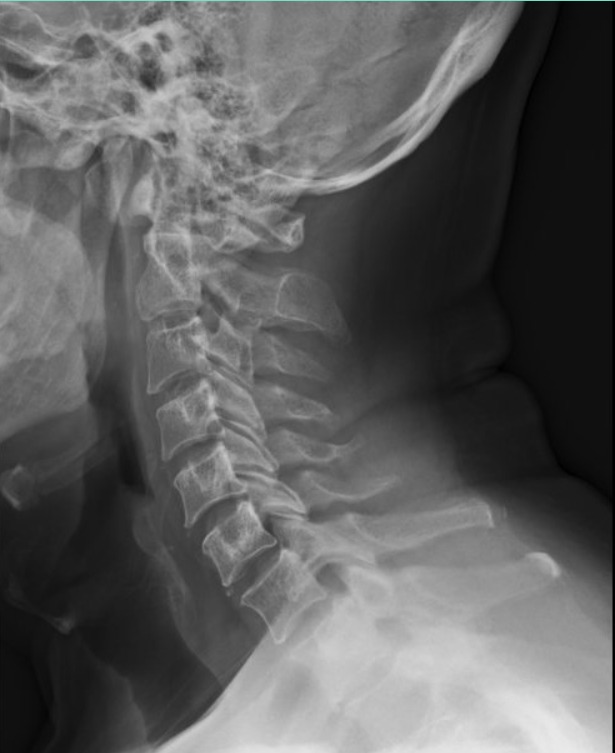

Tu columna sin dolor: tecnología láser y mejoría las primera 8 horas

¡Bienvenido a la Clínica de la Columna! Atendemos problemas en la columna lumbar, cervical y torácica con tratamientos personalizados y tecnología avanzada. Recupera tu movilidad y alivia el dolor con nuestro equipo de especialistas. ¡Agenda tu cita hoy y da el primer paso hacia una vida sin limitaciones!

En el Centro de la Columna Vertebral, el Dr. Gerardo Barajas, especialista en columna, realiza una evaluación detallada de pacientes que ya fueron tratados por otros médicos: revisa cirugías previas, resonancias, radiografías y tratamientos anteriores para determinar si el diagnóstico fue el adecuado y si el plan actual realmente es la mejor opción para ti.